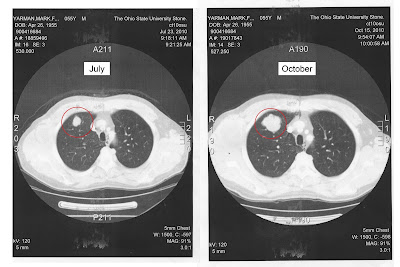

While we were there, my mom showed me some of the before and after scans of Mark's brain and lungs. The pictures do not paint an optimistic picture. I decided to scan two of the tumors in Mark's lungs to share with you the drastic changes that have taken place in just three short months.

Imagine that Mark is standing and facing you at your computer. His right shoulder is on the left of the screen and his left shoulder is on the right of your screen.

These are only two of several tumors Mark has in both his lungs and his brain. As I said, the pictures don't look good. I didn't post them to be a pessimist or make the situation seem hopeless, because we all have hope. We have to. But I thought you should see what we have seen so you understand the strength and prayers Mark needs!

| Tumor #1 in Mark's lungs (July & October) |

| Tumor #2 in Mark's lungs (July & October) |